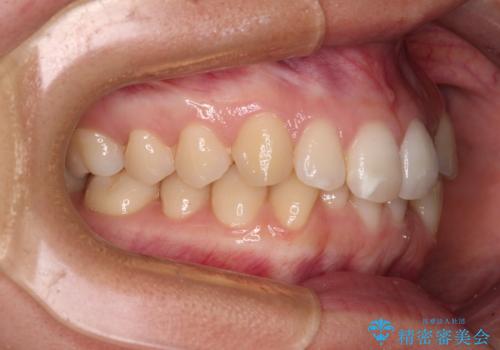

【モニター】前歯のデコボコとクロスバイト インビザラインによる矯正治療

- 上下のクロスバイトと前歯のデコボコを気にして来院された患者様です。

インビザラインを用い、IPR(歯と歯の間を削る)と歯列全体を拡大させることで、歯並びを整えていくこととしました。

下の歯が隠れてしまうほどでしたが、深い咬み合わせも改善され、顎への負担も軽減されました。